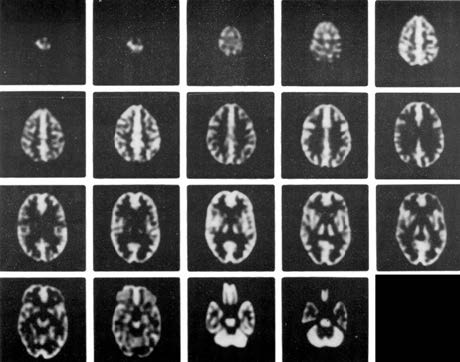

-在腦部SPECT及腦部PET的研究中,從解刨學(xué)角度精確的模擬放射性分布;在MRI研究中,精確模擬質(zhì)子密度及馳豫參數(shù)打的分布

Anatomically accurate simulation of radioactivity distribution for brain SPECT and brain PET studies* and distribution of proton density and relaxation parameters for brain MRI studies

-在血流和代謝研究中模擬正常灰質(zhì)和白質(zhì)的4:1攝取率(按部分體積效應(yīng)模擬)

Simulates 4:1 uptake ratio (by partial volume effect) seen for normal gray and white matter in flow and metabolic studies